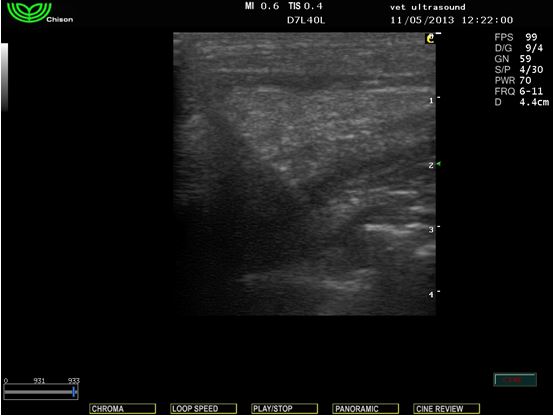

Στην υπερηχοτομογραφική εξέταση βρέθηκε ξένο σώμα το οποίο ξεκινούσε από το στομάχο και πρόβαλε κάτω από το δέρμα.